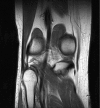

A 37-year-old man presented to the acute knee and sports medicine clinic with atraumatic lateral knee pain. He had point tenderness over the lateral aspect of his knee which had not settled with anti-inflammatory medications. Imaging revealed a large opaque lesion lateral to the knee and although there was no clear mechanism, injury to the posterolateral corner was considered. An MRI subsequently revealed a rare case of calcific tendinitis to the biceps femoris tendon insertion. This condition was self-limiting and did not require interventions such as steroid injections. This is the first reported case of calcific tendinitis of biceps femoris as a cause of acute knee pain.